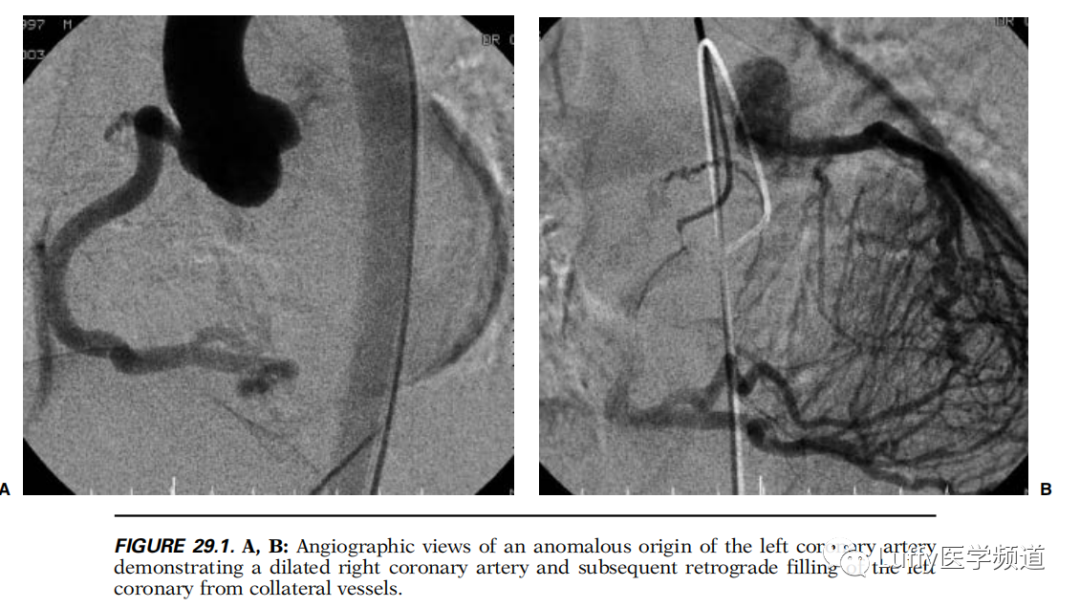

该病在婴儿早期常表现为充血性心力衰竭的症状和体征。进食后出现苍白、出冷汗。烦躁等所谓“婴儿心绞痛综合征”(syndrome of infantile angina)。大多病人表现呼吸困难、心动过速和肝肿大。由于心内膜下缺血和乳头肌失去功能,导致二尖瓣返流,心脏扩大,左心衰竭。所以X线胸片显示心脏明显扩大。心电图在I、AVL导联出现QR波形和T波倒置,表现为左心前侧壁心肌缺血、梗塞。B型超声有助于发现左冠状动脉起至肺动脉,彩色Doppler可显示左冠状动脉血液倒流至肺动脉。B型超声还有助于了解左心功能及乳头肌失去功能、二尖瓣返流程度等。主动脉造影检查,不仅可明确诊断,更可为手术提供依据,造影片上可显示右冠状动脉扩大,而左冠状动脉显影是通过来自右冠状动脉的侧支血管。